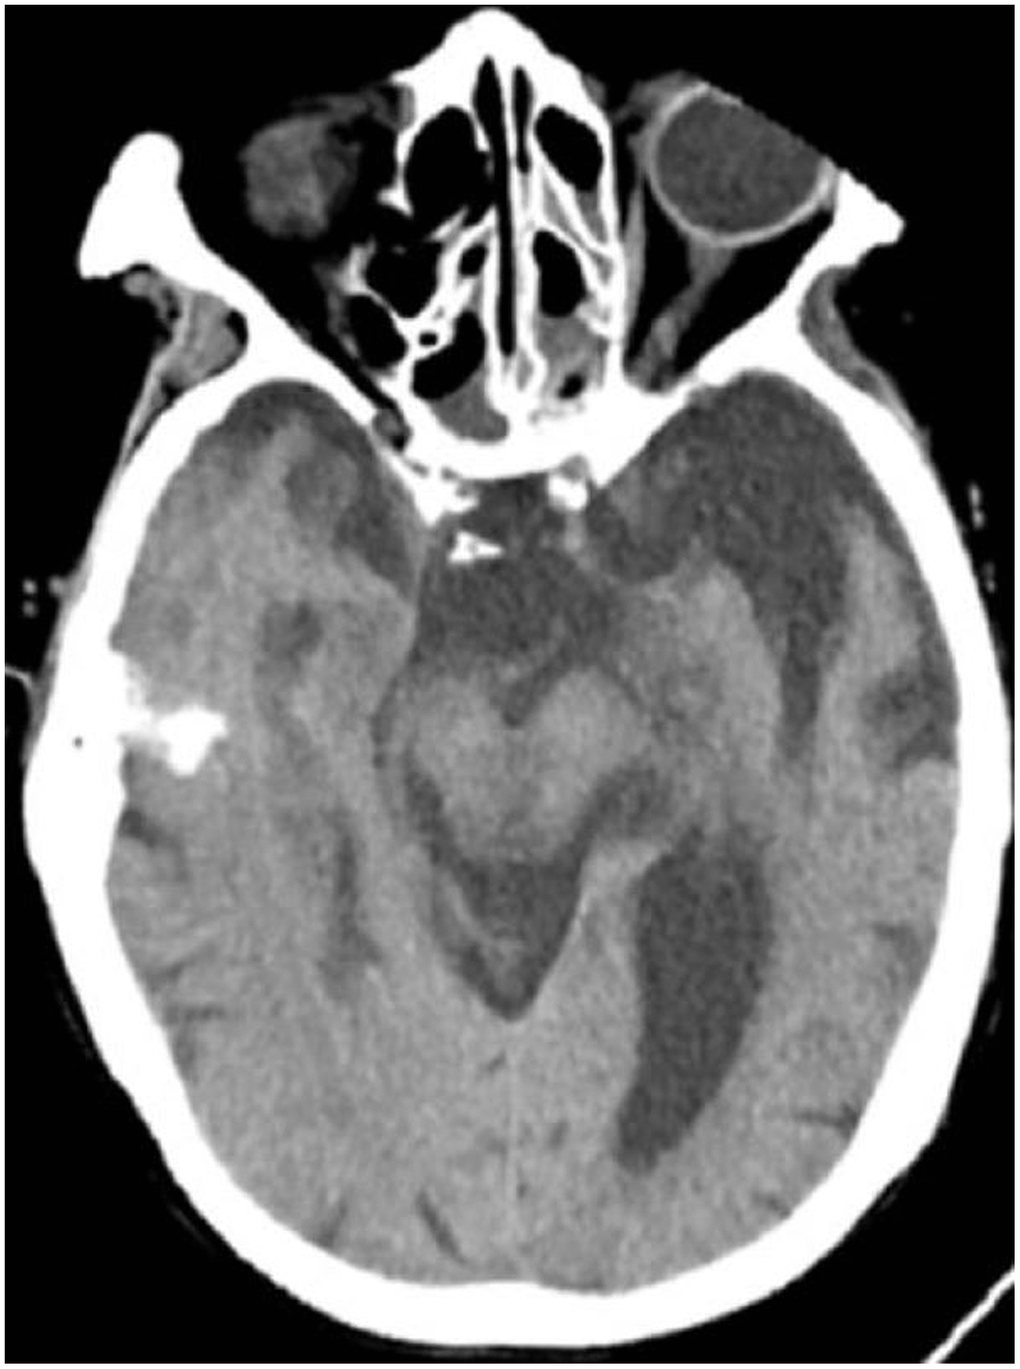

All patients were positive for the coronavirus nucleic acid test from pharyngeal swabs or blood. The blood lymphocyte counts and proportions of all patients were lower than normal (0.8×109/L) at the time of admission, and the white blood cell counts and proportions of six patients were higher than normal value (10×109/L). The blood D-dimer levels in all patients were higher than normal value (243 ng/mL) before neurological symptoms, and the C-reactive protein values in all patients were also higher than normal value (8000 μg/L). The chest CT of all patients showed flaky or frosted glass like- high-density shadow in lungs (Figures 1, 2), pleural effusion was seen in 2 cases (Figure 3), and no obvious abnormalities in 4 cases. The head CT imaging indicated that one patient had brainstem hemorrhage with ventricular cast and hydrocephalus (Figure 4), two patients had a large area of uniform low-density shadow on the frontotemporal lobe on the head CT (Figure 5), four patients had multiple flaky low-density shadow on the parietal lobe (Figure 6), one patient showed flaky low-density shadow in the pons (Figure 7), and three patients could see point-like low density shadow in basal ganglia (Figure 8).

Figure 4. Case 3, head CT imaging: one patient had brainstem hemorrhage with ventricular cast and hydrocephalus.

Figure 5. Case 2, a large area of uniform low-density shadow on the left frontotemporal lobe.